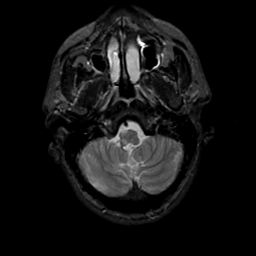

MR Study #20 October 6, 1991 -- Slice #7

[Home][Help][Clinical][Tour 1][Tour 2] Slice 7